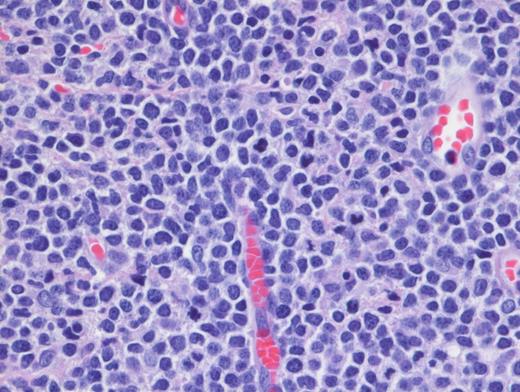

High-Power H&E. High-power demonstrates blastoid medium-sized lymphoid cells with dispersed chromatin (magnification x100).